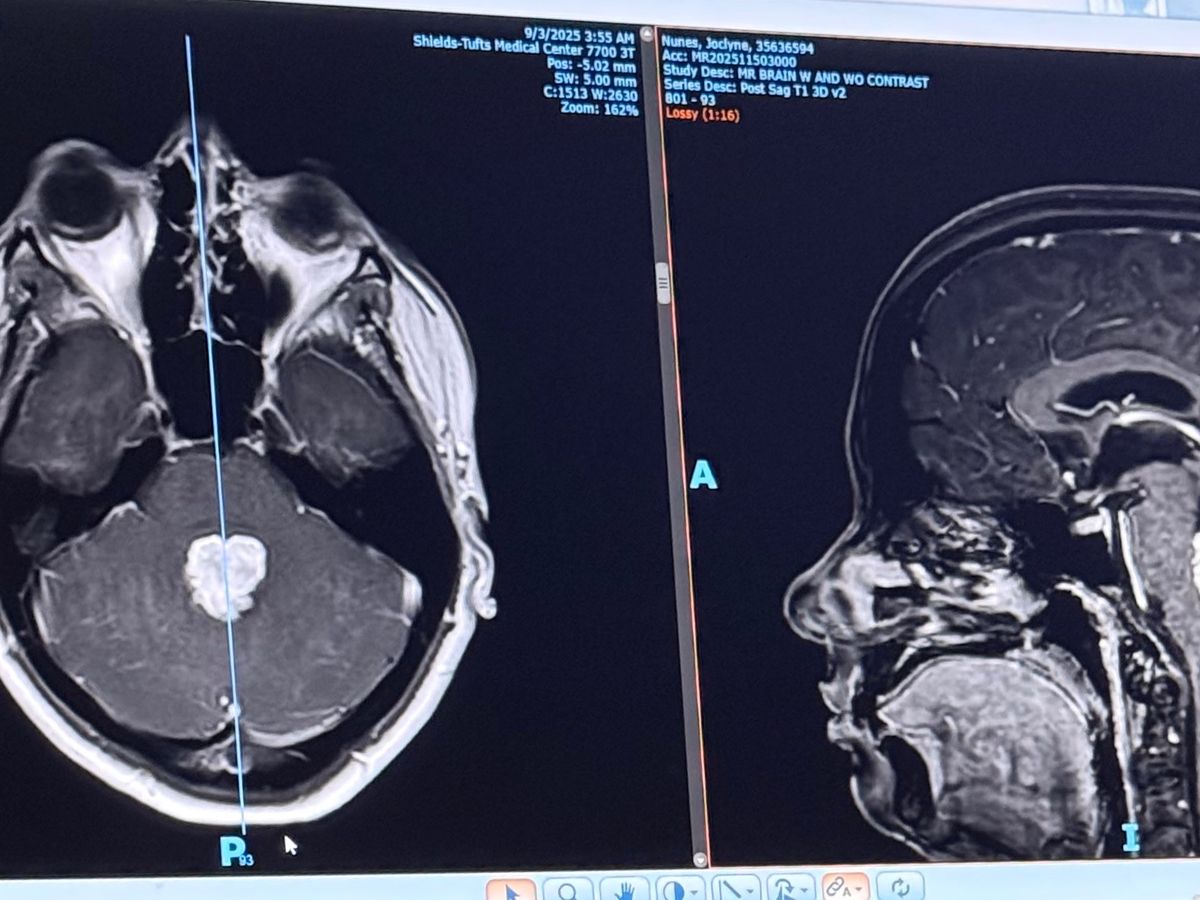

I am SO incredibly thankful that they did this, as it was determined that I had a nose-sized brain tumor - a choroid plexus papilloma with CSF obstruction. Me, someone who is young, healthy, and relatively active. I had some concerns, but I definitely didn’t expect to have a brain tumor that would need immediate removal.

36 hours later, I underwent brain surgery. I am thrilled to say that the entire tumor has been removed and is believed to be benign. Further genetic testing is being completed and I have a follow-up appointment in the coming days.